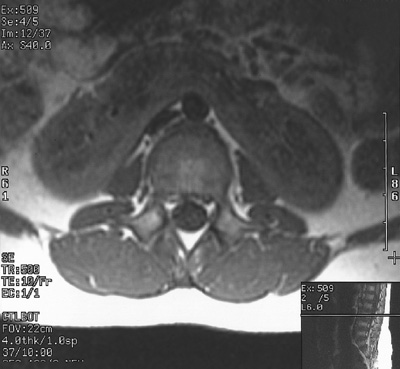

![]() | This abdominal MRI scan with contrast reveals a horseshoe kidney bridging across the midline. In this view the contrast media is excreted into and highlights the renal pelves of the fused kidney. The path of the ureters over the top of the bridge between the fused lower poles is potentially a point of obstruction. |